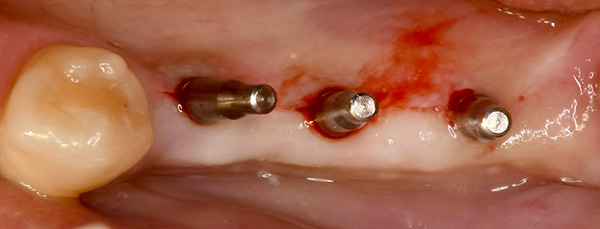

オペ前の口腔内写真。

抜糸の来院ができないため、切らない縫わない「フラップレスインプラント」で処置することにしました。

直径2ミリのバーで小さい穴を3箇所あけます。

直径2ミリのピンを挿入します。

CT写真を撮影して、インプラントを埋め込む位置に狂いがないかを確認します。

徐々に太いバーで顎骨を削っていき、インプラントを埋入します。

なお、腫れと痛みを最小限にするために、「ショートインプラント」を使用しました。

ショートインプラントは文字通り短いので、顎骨を削る量を少なくできます。

インプラント埋入後のCT写真。

想定通りの位置に3本のインプラントが埋め込まれています。

歯茎を回復させるためのパーツをセットして、オペ終了となります。